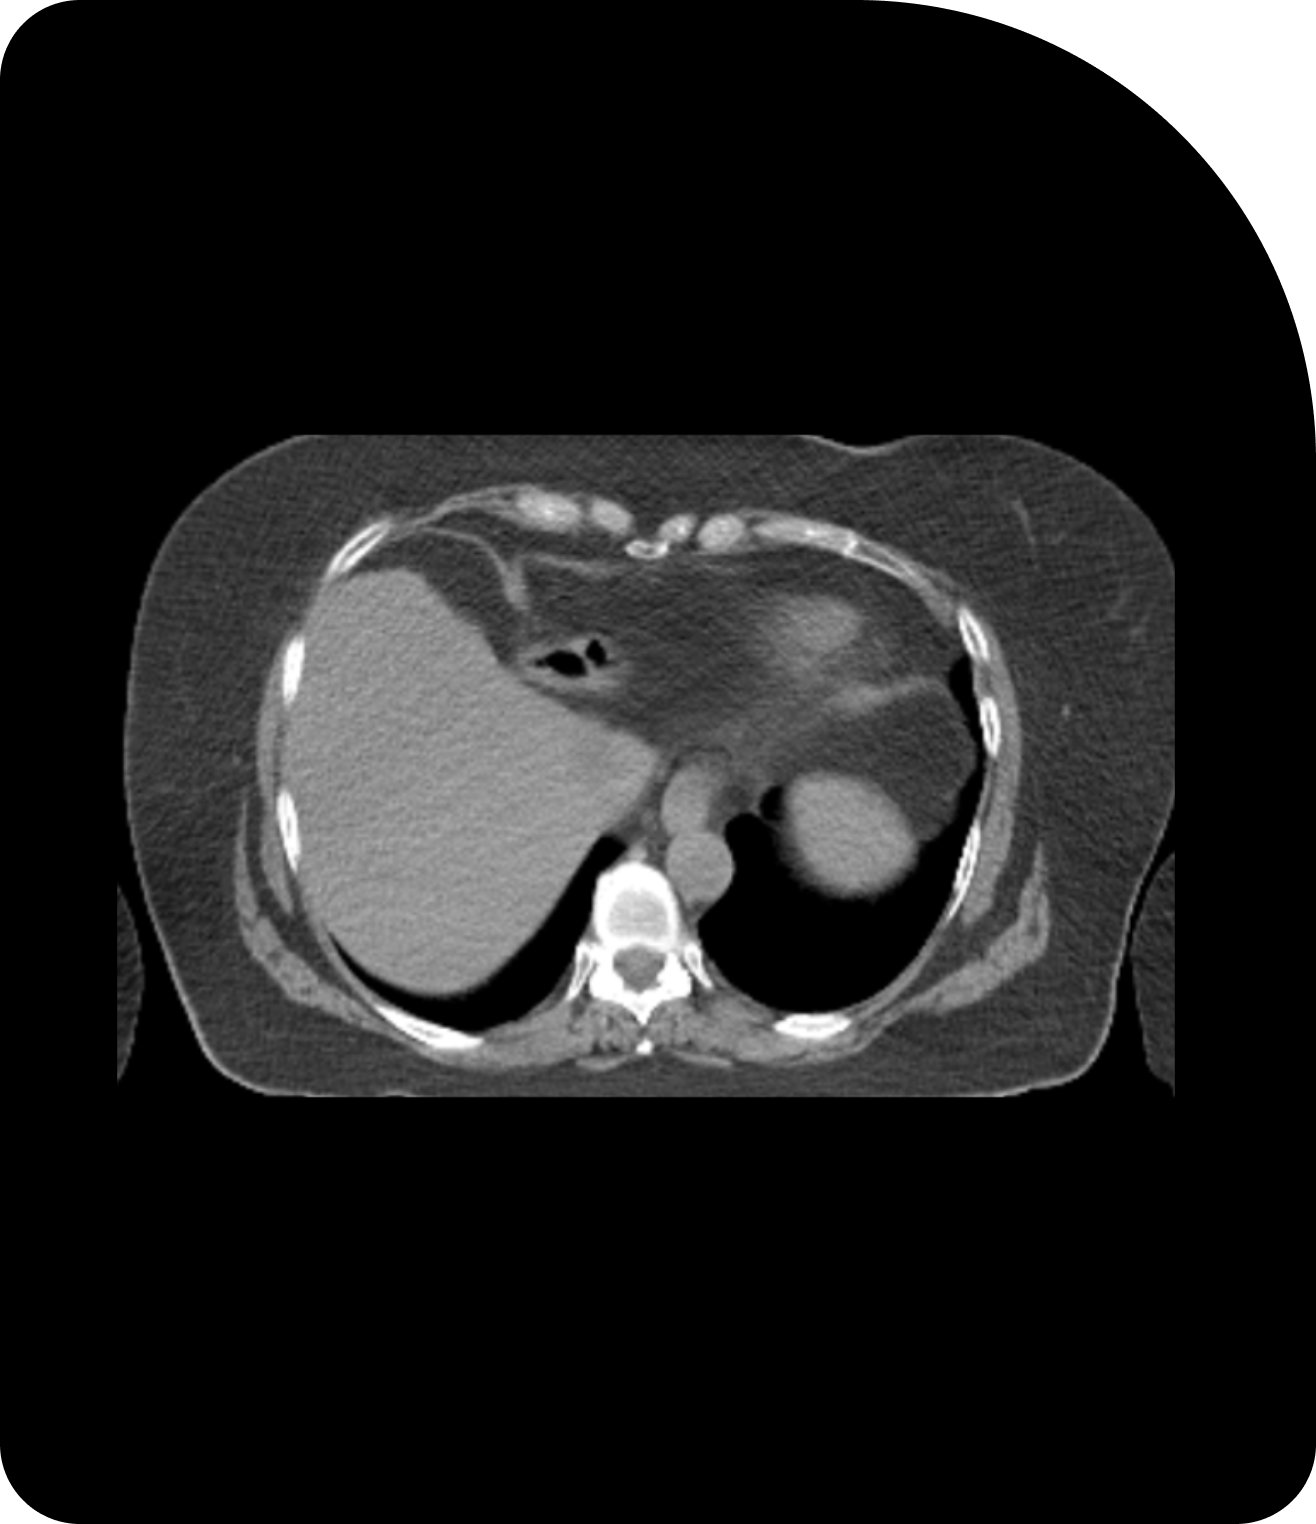

CT

Standard imaging provides a baseline view for treatment planning.

CBCT

Cone Beam CT adds in-room imaging to support daily patient setup.

Clearer images mean more accurate targeting. Compare CT, CBCT, and MRI to see the difference.